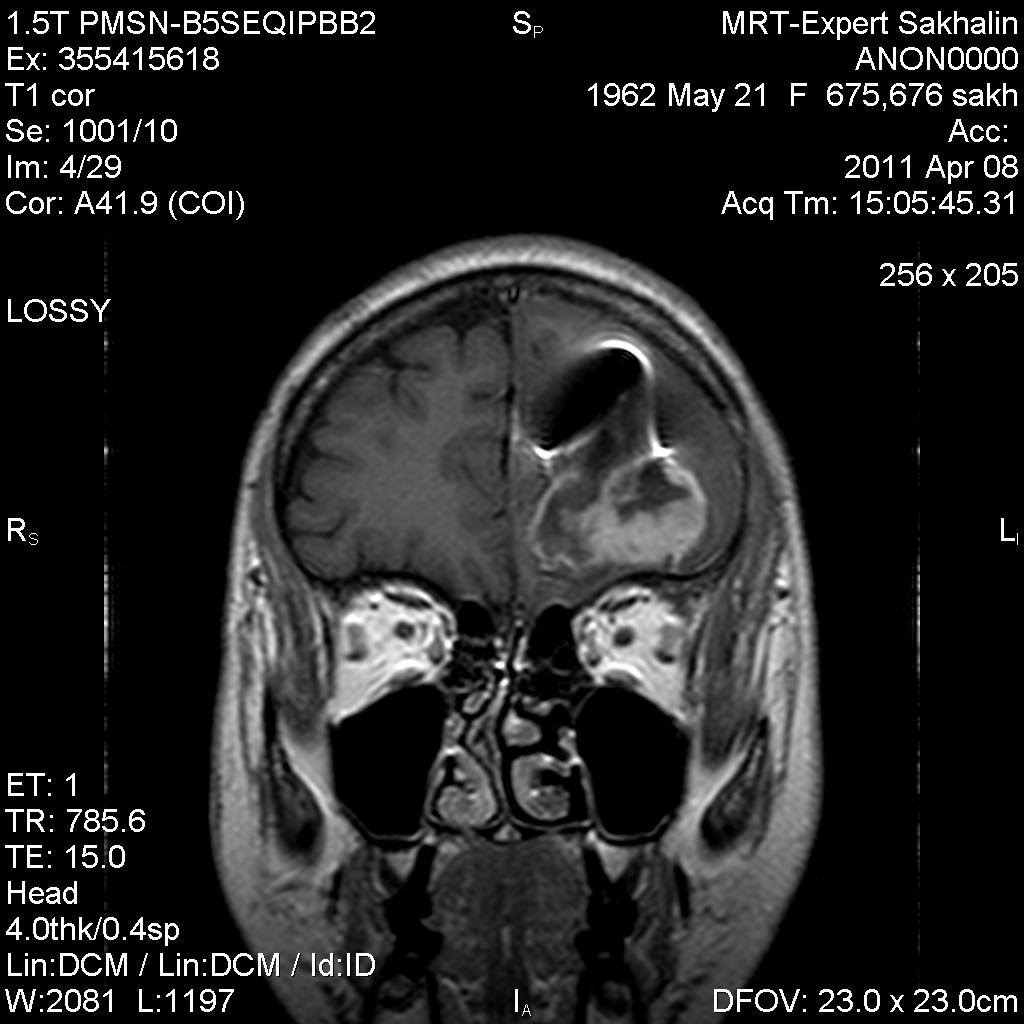

Женщина с жалобами на снижение зрения.В анамнезе 2 операции по удалению образования левой лобной доли.В одной выписке-анапластическая астроцитома, в сегоднящней-олигодендроглиома.

первое исследование-апрель 2011г.

Третий  рецидив за год)))